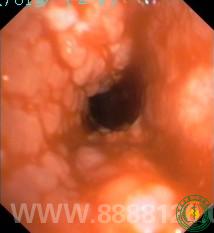

呼吸一科支气管镜中心成功钳取右中间支气管异物一例

呼吸一科支气管镜中心成功钳取右中间支气管异物一例6307